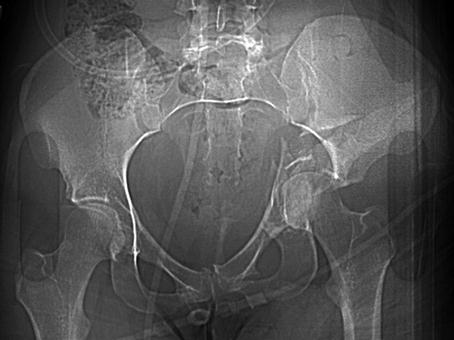

Excessive loading of the proximal femur through the femoral head causes the acetabulum to fracture. In this example, the left-sided unstable acetabular fracture fragments are displaced significantly as the proximal femur intrudes medially into the pelvis